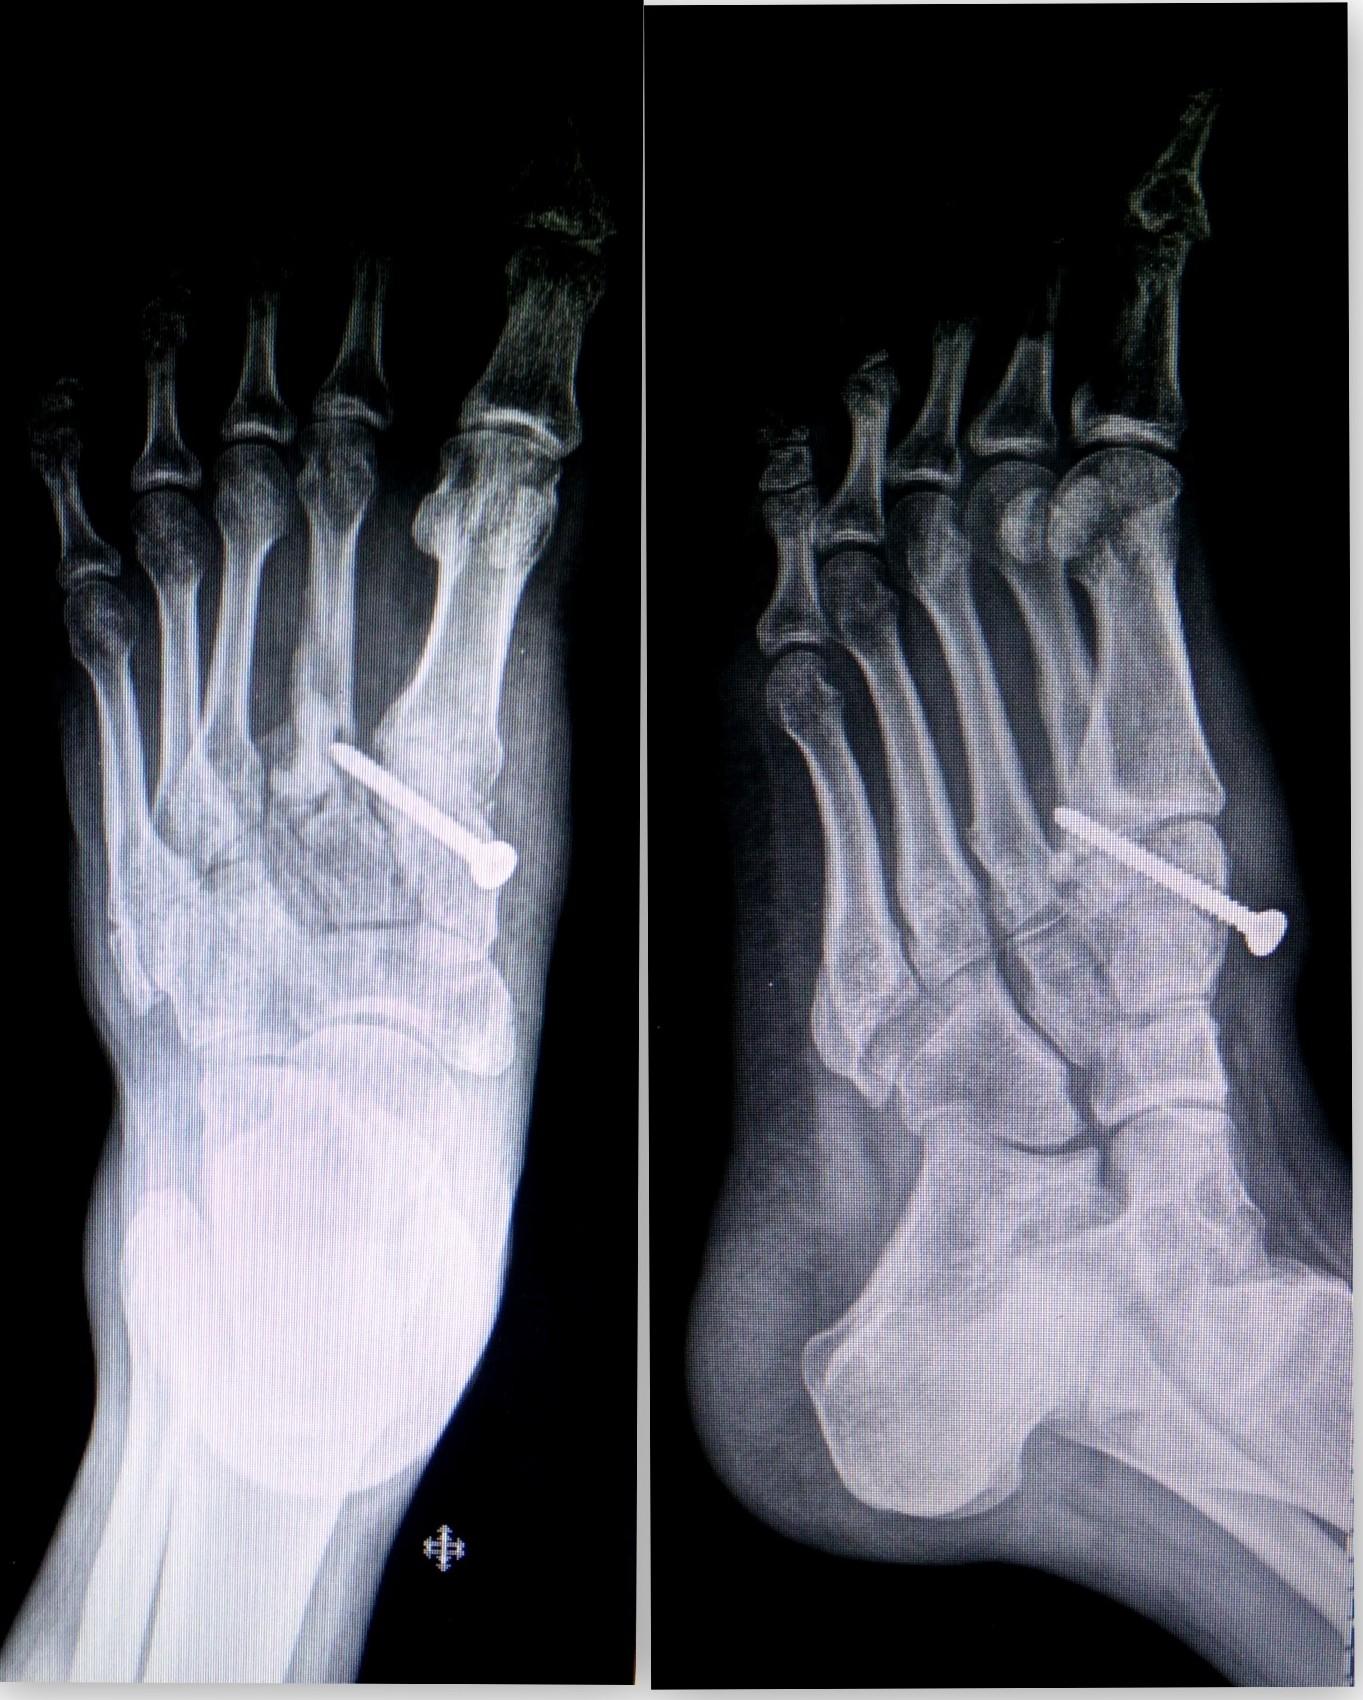

Your foot and ankle orthopaedic surgeon may recommend surgery for a lisfranc injury if your midfoot joints are not lined up anatomically. A lisfranc injury, also known as lisfranc fracture, is an injury of the foot in which one or more of the metatarsal bones are displaced from the tarsus. Some injuries of this type may require emergency surgery. With indirect trauma, force is transmitted to. They can take a long time to heal and may also require surgery. A lisfranc injury, also known as lisfranc fracture, is an injury of the foot in which one or more of the metatarsal bones are displaced from the tarsus. Complications can and often arise following lisfranc injuries. The injury was first noticed in the early 1800s by the french surgeon jacques lisfranc. Aug 24, 2017 · a lisfranc fracture is a type of bone fracture that occurs in the middle of the foot, affecting ligaments and metatarsals. Injury mechanisms are varied and include direct crush injury or an indirect load onto a plantarflexed foot 3. The injury is named after jacques lisfranc de st. Diagnosis is confirmed by radiographs which may show widening of the interval between the 1st and 2nd ray.

The lisfranc ligament is a strong band attaching the medial cuneiform to the 2 nd metatarsal base on the foot's plantar aspect. Some injuries of this type may require emergency surgery. The injury was caused when soldiers were thrown of their horses and their foot was stuck into the stirrup. A lisfranc injury, also known as lisfranc fracture, is an injury of the foot in which one or more of the metatarsal bones are displaced from the tarsus. Aug 24, 2017 · a lisfranc fracture is a type of bone fracture that occurs in the middle of the foot, affecting ligaments and metatarsals. They can take a long time to heal and may also require surgery. A lisfranc injury, also known as lisfranc fracture, is an injury of the foot in which one or more of the metatarsal bones are displaced from the tarsus. Diagnosis is confirmed by radiographs which may show widening of the interval between the 1st and 2nd ray. The goals of lisfranc surgery are to put the bones back into their original position and restore the foot's normal alignment. Injury mechanisms are varied and include direct crush injury or an indirect load onto a plantarflexed foot 3. A lisfranc injury is often mistaken for a simple sprain, especially if the injury is a result of a straightforward twist and fall.

Diagnosis is confirmed by radiographs which may show widening of the interval between the 1st and 2nd ray. They can take a long time to heal and may also require surgery. Now automobile accidents, falls and sport injuries can also lead to an injury on the lisfranc joint. A lisfranc injury, also known as lisfranc fracture, is an injury of the foot in which one or more of the metatarsal bones are displaced from the tarsus. A possible early complication following the injury is compartment syndrome, in which pressure builds up within the tissues of the foot, requiring immediate surgery to prevent tissue damage. However, injury to the lisfranc joint is not a simple sprain that should be simply walked off. it is a severe injury that may take many months to heal and may require surgery to treat. Some injuries of this type may require emergency surgery. The goals of lisfranc surgery are to put the bones back into their original position and restore the foot's normal alignment. The lisfranc ligament is a strong band attaching the medial cuneiform to the 2 nd metatarsal base on the foot's plantar aspect. We would like to show you a description here but the site won't allow us. Aug 24, 2017 · a lisfranc fracture is a type of bone fracture that occurs in the middle of the foot, affecting ligaments and metatarsals. The injury was first noticed in the early 1800s by the french surgeon jacques lisfranc.

Injury mechanisms are varied and include direct crush injury or an indirect load onto a plantarflexed foot 3. The injury is named after jacques lisfranc de st. A lisfranc injury, also known as lisfranc fracture, is an injury of the foot in which one or more of the metatarsal bones are displaced from the tarsus. The injury was first noticed in the early 1800s by the french surgeon jacques lisfranc. A lisfranc injury is a tarsometatarsal fracture dislocation characterized by traumatic disruption between the articulation of the medial cuneiform and base of the second metatarsal. A possible early complication following the injury is compartment syndrome, in which pressure builds up within the tissues of the foot, requiring immediate surgery to prevent tissue damage. Aug 24, 2017 · a lisfranc fracture is a type of bone fracture that occurs in the middle of the foot, affecting ligaments and metatarsals. We would like to show you a description here but the site won't allow us. Diagnosis is confirmed by radiographs which may show widening of the interval between the 1st and 2nd ray. However, injury to the lisfranc joint is not a simple sprain that should be simply walked off. it is a severe injury that may take many months to heal and may require surgery to treat. With indirect trauma, force is transmitted to. The injury was caused when soldiers were thrown of their horses and their foot was stuck into the stirrup. A lisfranc injury is often mistaken for a simple sprain, especially if the injury is a result of a straightforward twist and fall.

The goals of lisfranc surgery are to put the bones back into their original position and restore the foot's normal alignment.

Diagnosis is confirmed by radiographs which may show widening of the interval between the 1st and 2nd ray.